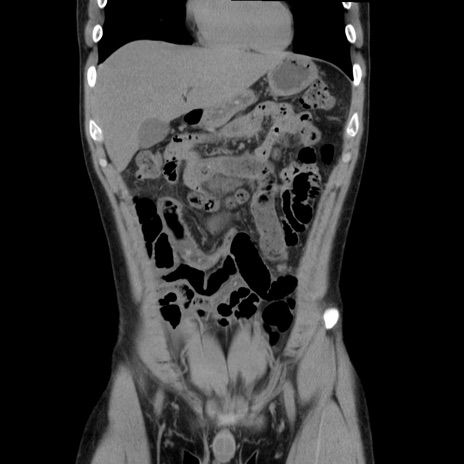

症例36(冠状断像)

【症例】20歳代 男性

【主訴】心窩部痛

【現病歴】今朝より上腹部痛あり。一旦軽快していたが再度出現したため救急要請。昨日夕に白身の魚を含む刺身を食べた。

【身体所見】BP 136/89mmHg、HR 74/min、BT 37.0℃、腹部:膨満、軟、心窩部に圧痛あり。反跳痛なし、筋性防御なし、腸雑音やや亢進あり。

【データ】WBC 17700、CRP 0.48

横断像